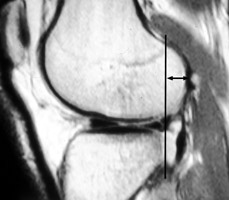

ACL Tear

The anterior cruciate ligament runs obliquely within the lateral aspect of the intercondylar notch, attaching to the inner aspect of the lateral femoral condyle proximally and to the anterior aspect of the intercondylar eminence of the tibia distally. An anterior cruciate ligament-deficient knee allows the tibia to undergo subluxation anteriorly relative to the femur. This is the MR equivalent of the anterior drawer sign.